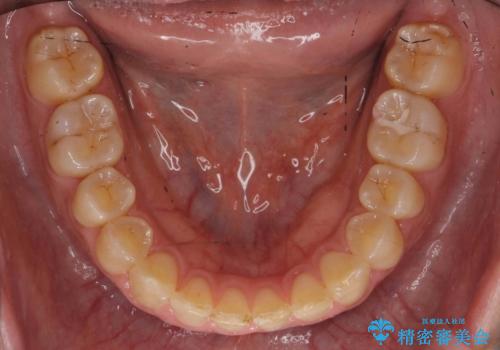

奥歯が1歯対1歯で、過蓋咬合を呈していました。

レントゲンで、右上4番の近心の垂直的骨欠損があり、抜歯を行うこととしました。

垂直的骨欠損は咬み合わせから起こったものと推察されました。